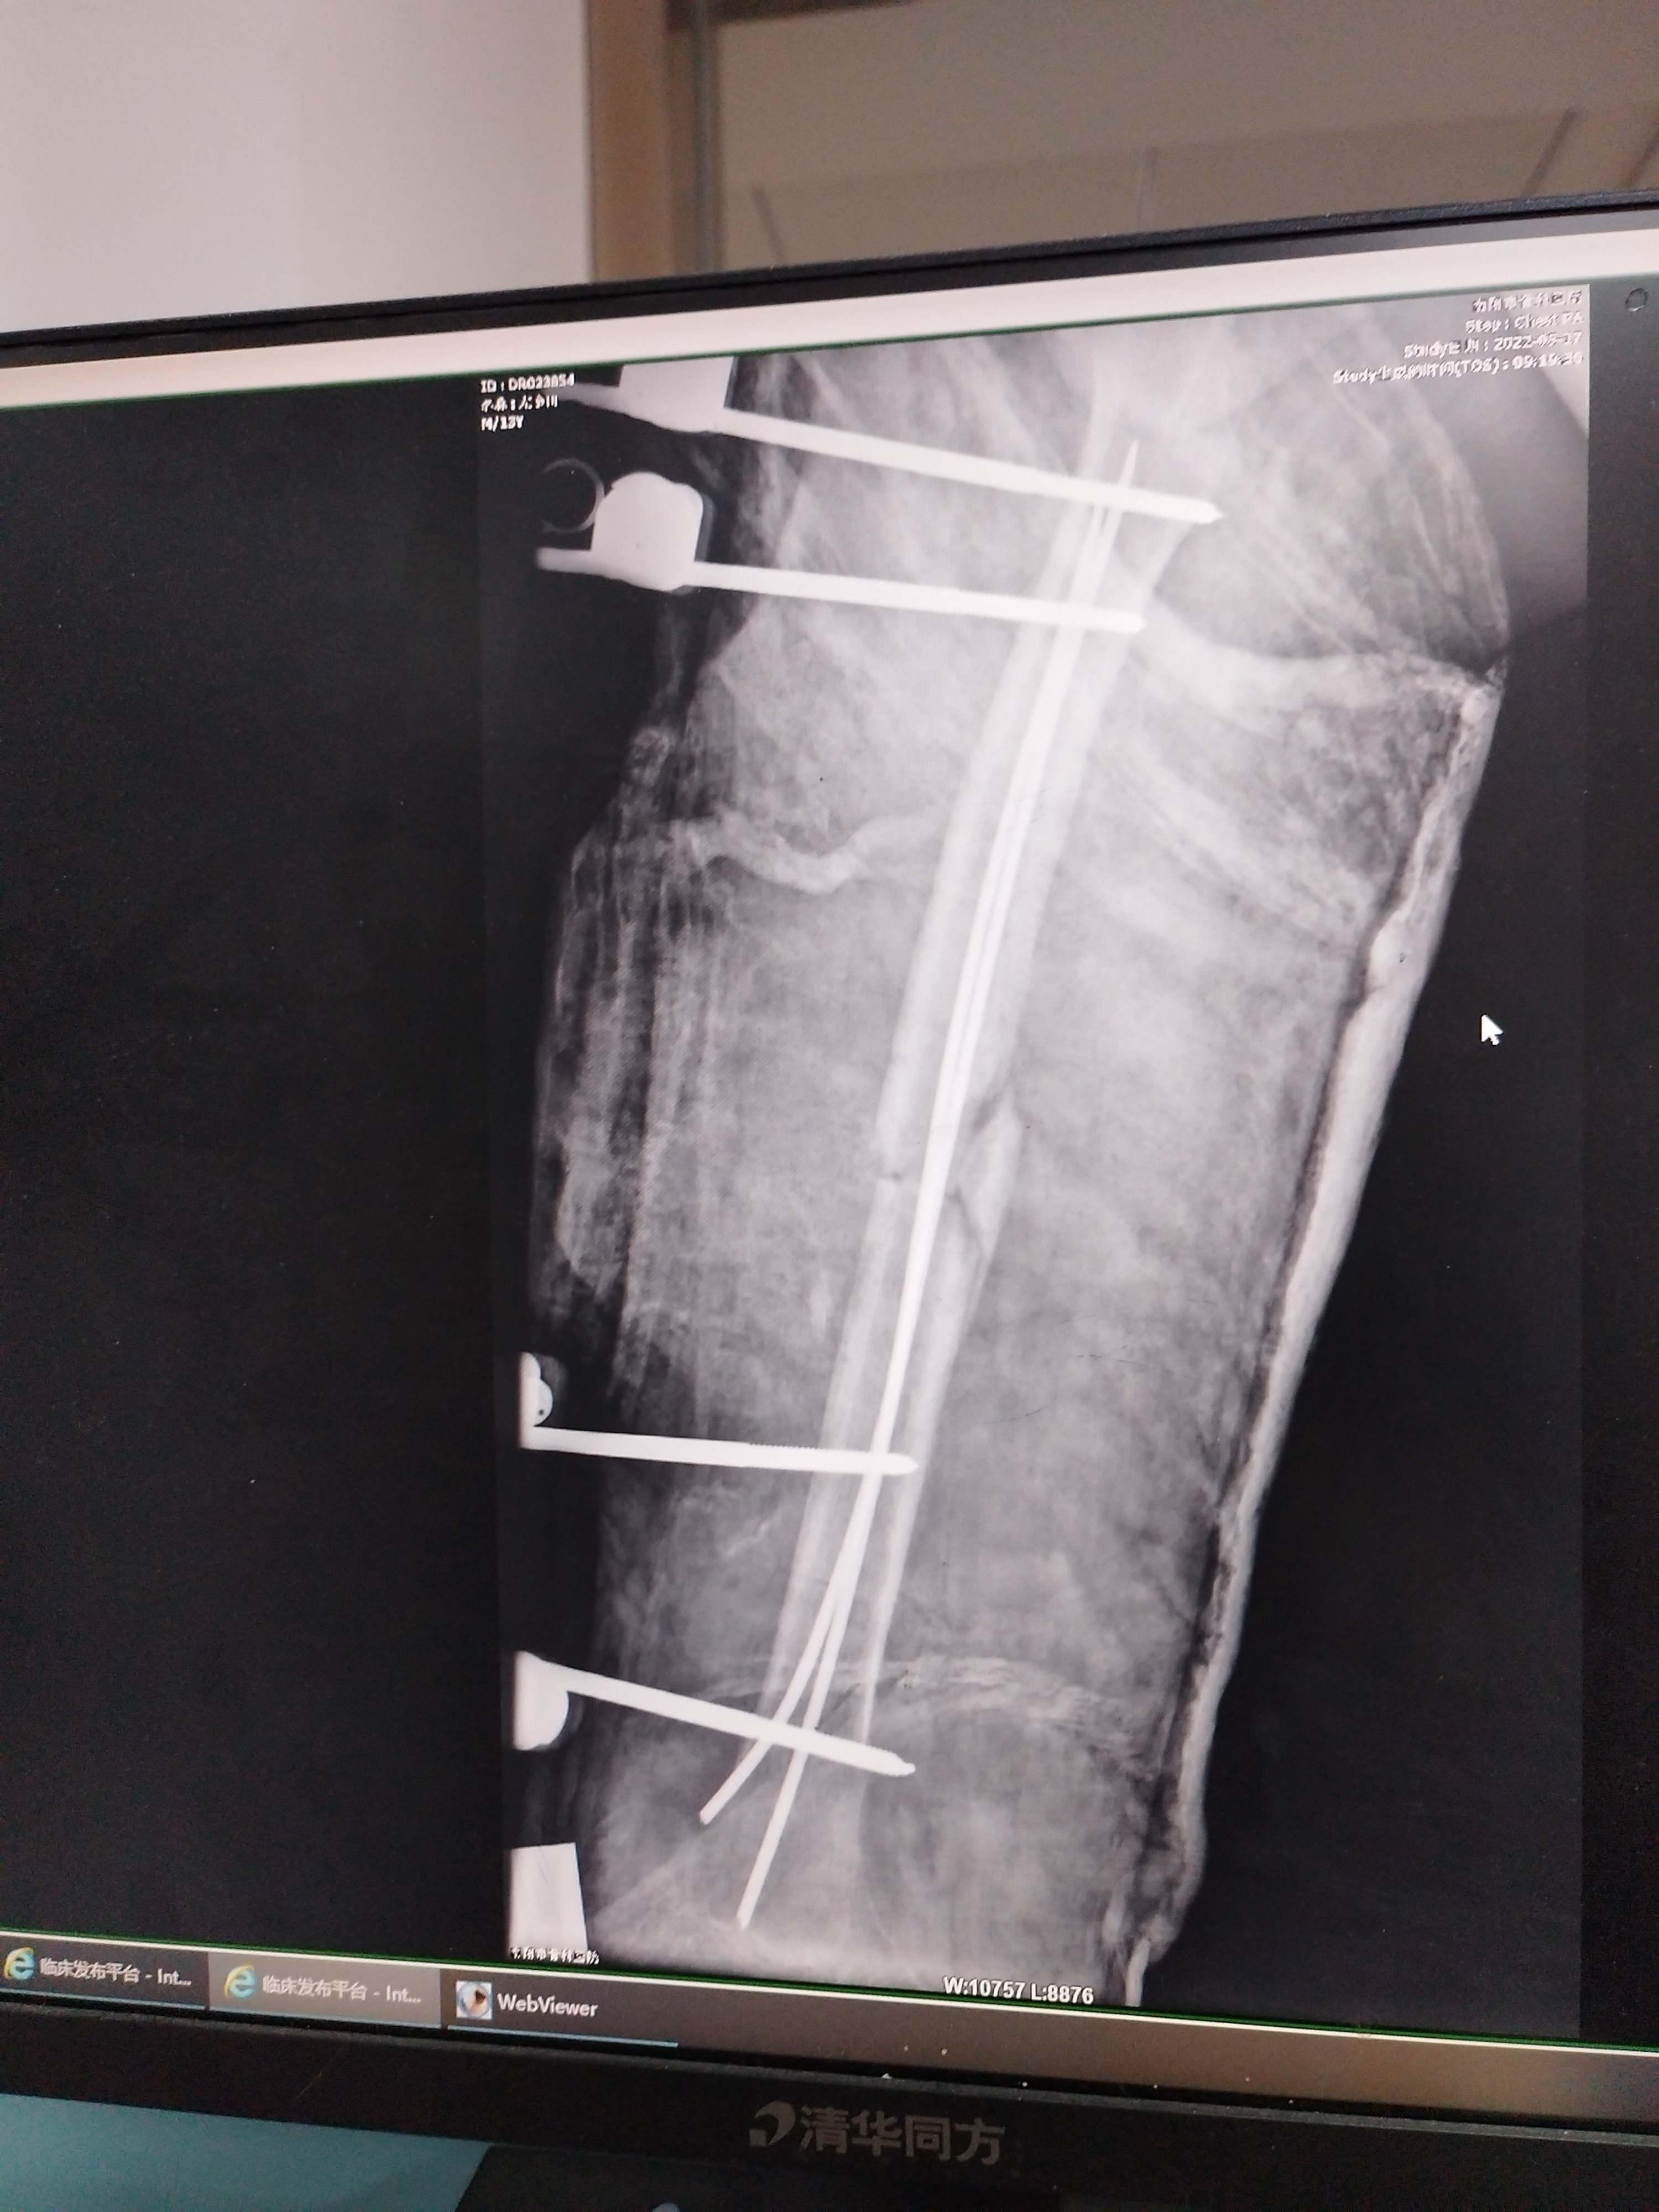

主诉:右下肢骨折术后肢体短缩2年。

2年前因“右股骨干骨折”在当地医院行“弹性髓内针+外架+石膏固定术”术后半年拆外架,1年拆弹性髓内针。目前左下肢短缩约4cm,为求治疗来院。